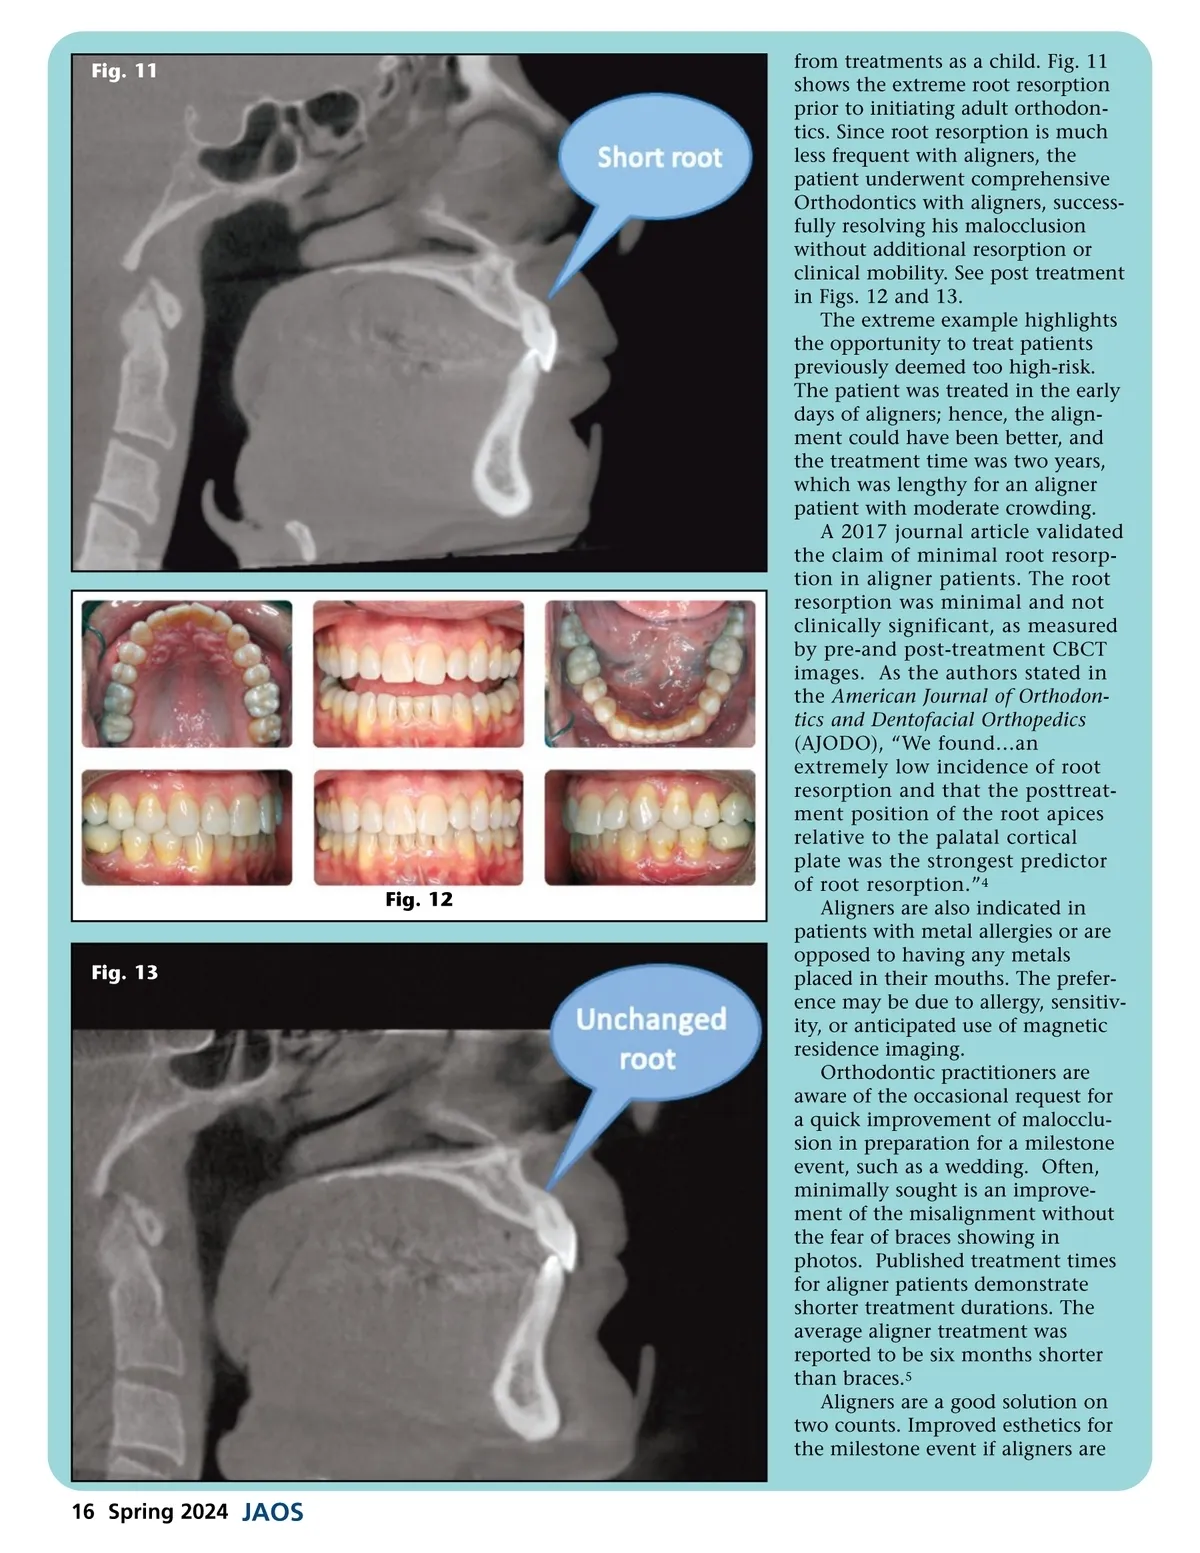

Fig. 11 Fig. 12 Fig. 13 from treatments as a child. Fig. 11 shows the extreme root resorption prior to initiating adult orthodon-tics. Since root resorption is much less frequent with aligners, the patient underwent comprehensive Orthodontics with aligners, success-fully resolving his malocclusion without additional resorption or clinical mobility. See post treatment in Figs. 12 and 13. The extreme example highlights the opportunity to treat patients previously deemed too high-risk. The patient was treated in the early days of aligners; hence, the align-ment could have been better, and the treatment time was two years, which was lengthy for an aligner patient with moderate crowding. A 2017 journal article validated the claim of minimal root resorp-tion in aligner patients. The root resorption was minimal and not clinically significant, as measured by pre-and post-treatment CBCT images. As the authors stated in the American Journal of Orthodon-tics and Dentofacial Orthopedics (AJODO), “We found…an extremely low incidence of root resorption and that the posttreat-ment position of the root apices relative to the palatal cortical plate was the strongest predictor of root resorption.” 4 Aligners are also indicated in patients with metal allergies or are opposed to having any metals placed in their mouths. The prefer-ence may be due to allergy, sensitiv-ity, or anticipated use of magnetic residence imaging. Orthodontic practitioners are aware of the occasional request for a quick improvement of malocclu-sion in preparation for a milestone event, such as a wedding. Often, minimally sought is an improve-ment of the misalignment without the fear of braces showing in photos. Published treatment times for aligner patients demonstrate shorter treatment durations. The average aligner treatment was reported to be six months shorter than braces. 5 Aligners are a good solution on two counts. Improved esthetics for the milestone event if aligners are 16 Spring 2024 JAOS